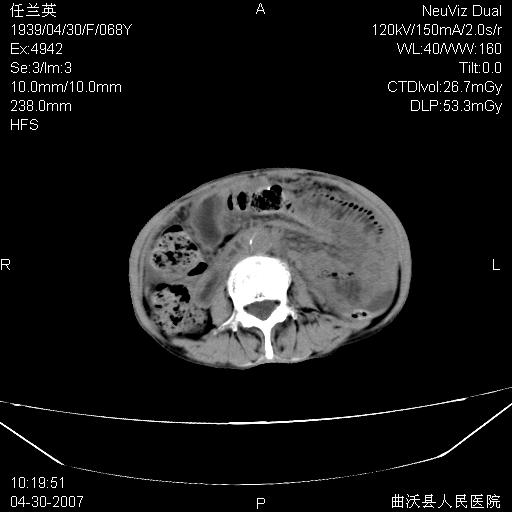

患者,女,68岁,感觉腹部憋涨发硬数天,查b超发现左盆腔有囊性肿物和少量腹水,行ct检查

1.考虑卵巢肿瘤并腹腔广泛性转移可能性大;

2.腹盆腔少量积液。

支持左侧卵巢恶性肿瘤伴网膜、腹膜广泛转移。

网膜、腹膜广泛转移考虑来源于左侧卵巢癌可能性大。不除外来源于消化系的肿瘤。

难的一见 典型 - 网膜饼  冰冻骨盆 可以当教学片了